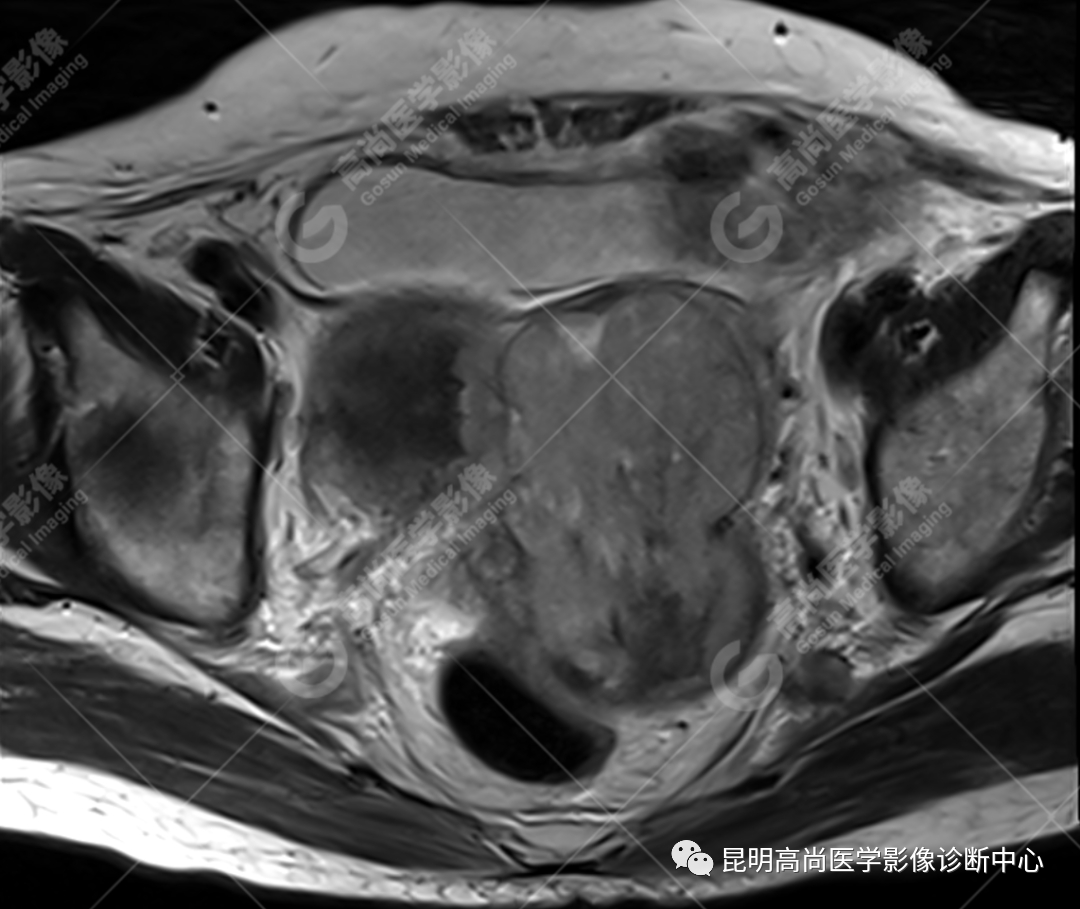

检查图像

影像诊断

子宫、附件未见显示;下腹部及盆腔内巨大占位,考虑恶性肿瘤,肉瘤可能,阴道及肛管受侵,建议活检。

MRI 表现

不规则菜花状或息肉状肿物,子宫内膜正常 T2WI 清晰连续的高信号消失,取而代之是中高、高信号,不均匀混杂信号,信号强度低于内膜正常信号强度,T1WI 上内膜信号增高,子宫肌层明显变薄,未受侵者肌层信号均匀,因肿物组织来源不同,病变信号复杂,以 T2WI 表现为等高混杂信号为主。因病灶较大,可合并囊变坏死及肿瘤出血。

各学者认为子宫内膜肿瘤内部不同的强化方式能够提高子宫癌肉瘤的诊断概率,多数学者认为病灶中早期明显强化,并持续强化的区域是肿瘤中的间质成分的强化特点,而上皮成分一般呈轻度强化。